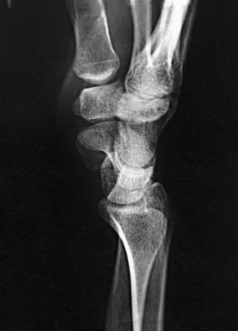

The elbow joint proper includes the proximal radioulnar articulation and the articulations between the humerus and the radius and ulna. The three joints are enclosed in a common capsule. The trochlea of the humerus articulates with the ulna at the trochlear notch. The capitulum of the humerus articulates with the flattened head of the radius. The humeroulnar and humeroradial articulations form a synovial hinge joint and allow only flexion and extension movement (Figs. 4-10 and 4-11, A). The proximal humerus and its articulations are described with the shoulder girdle in Chapter 5.

The three areas of fat1,2 associated with the elbow joint can be visualized only in the lateral projection (Fig. 4-11, B and C). The posterior fat pad covers the largest area and lies within the olecranon fossa of the posterior humerus. The superimposed coronoid and radial fat pads, which lie in the coronoid and radial fossae of the anterior humerus, form the anterior fat pad. The supinator fat pad is positioned anterior to and parallel with the anterior aspect of the proximal radius.

When the elbow is flexed 90 degrees for the lateral projection, only the anterior and supinator fat pads are visible, and the posterior fat pad is depressed within the olecranon fossa. The anterior fat pad resembles a teardrop, and the supinator fat pad appears as shown in Fig. 4-11, B. The fat pads become significant radiographically when an elbow injury causes effusion and displaces the fat pads or alters their shape. Visualization of the posterior fat pad is a reliable indicator of elbow pathology. Exposure factors designed to show soft tissues are extremely important on lateral elbow radiographs because visualization of the fat pads may be the only evidence of injury.